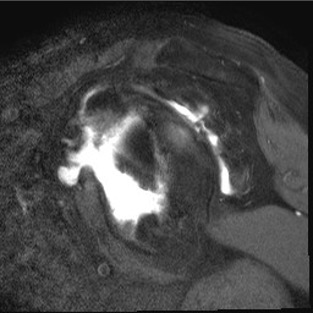

MRI

Rotator cuff tears

MRI with supraspinatus tear, Hill Sachs lesion and significant glenoid bony deficiency